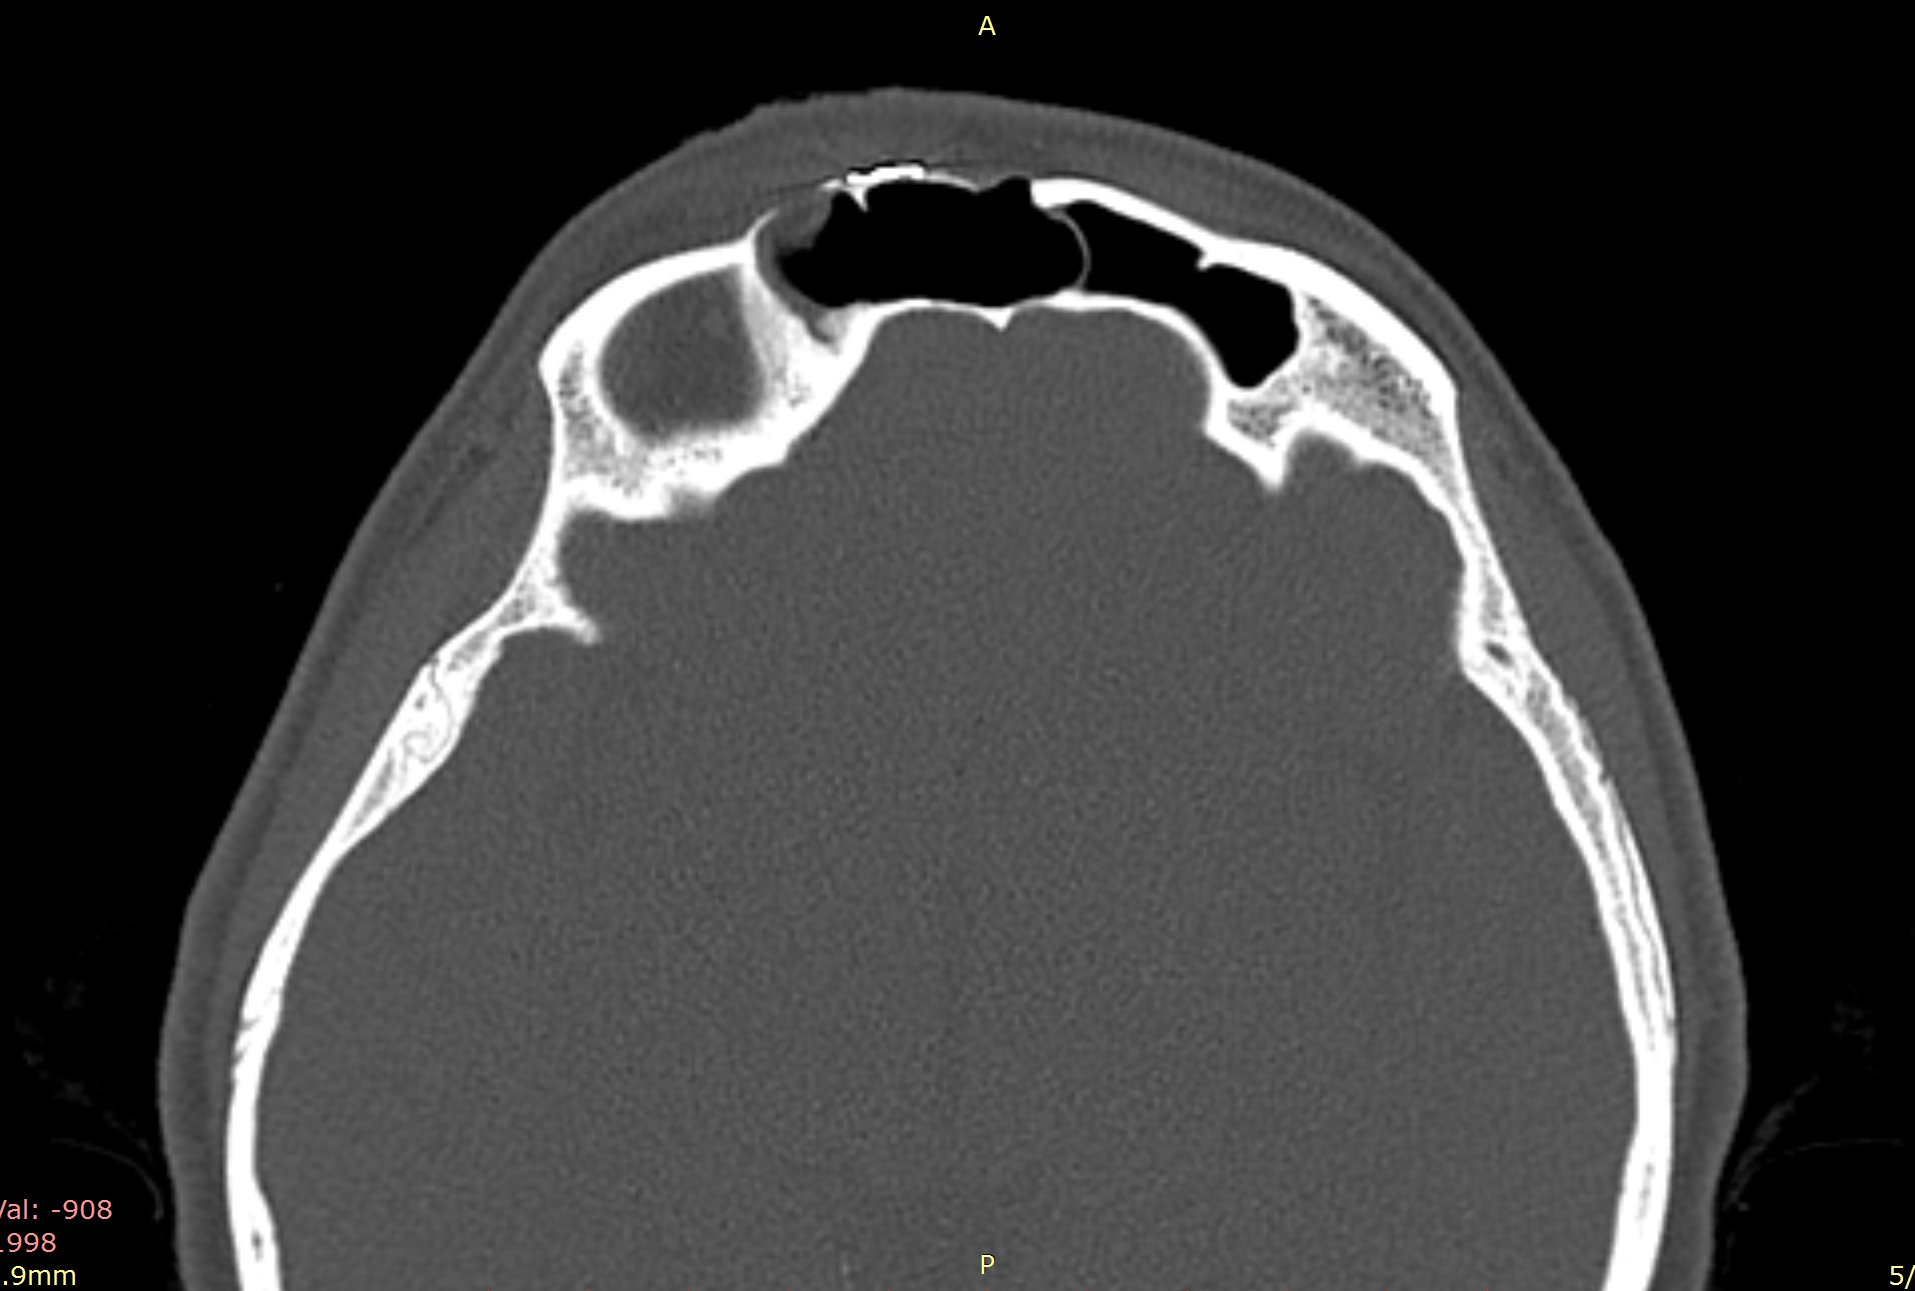

Examenul clinic ORL și examenele imagistice complementare (CT, RMN sinusuri paranazale) pun în evidență o formațiune tumorală osteogenică a sinusului frontal drept, protruzivă în unghiul supero-intern al orbitei, extinsă medial către sinusul frontal stâng.